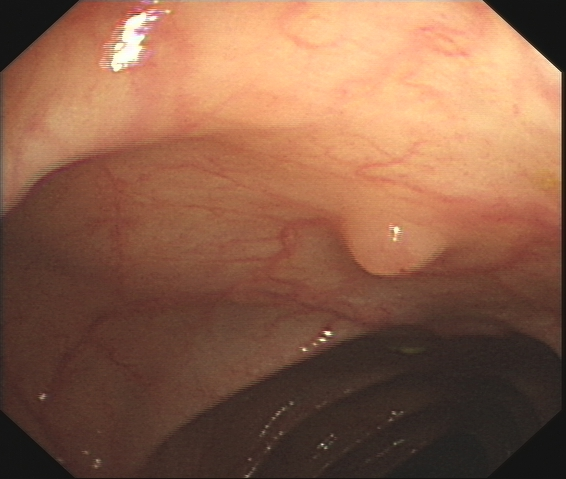

We improved an existing end-to-end polyp detection model with better average precision validated by different data sets with trivial cost on detection speed. Previous work on detecting polyps within colonoscopy \cite{Chen2018} provided an efficient end-to-end solution to alleviate doctor's examination overhead. However, our later experiments found this framework is not as robust as before as the condition of polyp capturing varies. In this work, we conducted several studies on data set, identifying main issues that causes low precision rate in the task of polyp detection. We used an optimized anchor generation methods to get better anchor box shape and more boxes are used for detection as we believe this is necessary for small object detection. A alternative backbone is used to compensate the heavy time cost introduced by dense anchor box regression. With use of the attention gate module, our model can achieve state-of-the-art polyp detection performance while still maintain real-time detection speed.